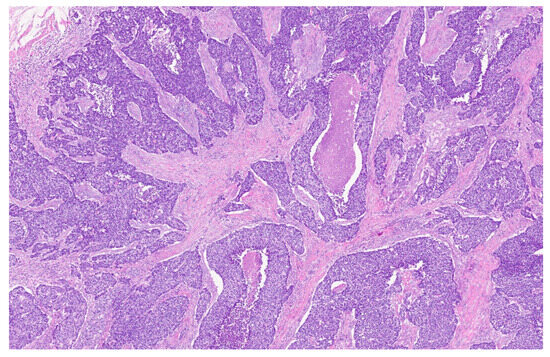

| 3 | Microlaryngoscopy with biopsy |